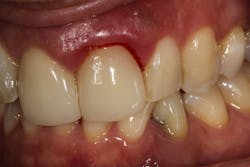

The importance of a staged treatment approach in periodontal treatment cannot be overemphasized. As with any wound, treatment begins with cleaning the wound as well as possible. That is what occurs in the initial cleaning or scaling and root planing visit. When that doesn’t work, bleeding and/or deepening of the periodontal pocket could result. The key is not to give up. It just means another diagnosis must be done, and treatment with more sophisticated instrumentation may be necessary to achieve the desired result.

All three authors have seen many patients throughout their careers who have been told that nothing can be done and that teeth need to be removed due to “uncontrollable periodontal disease.” In most cases, this has proven to be false. We have examined these patients and treated them with outstanding success.